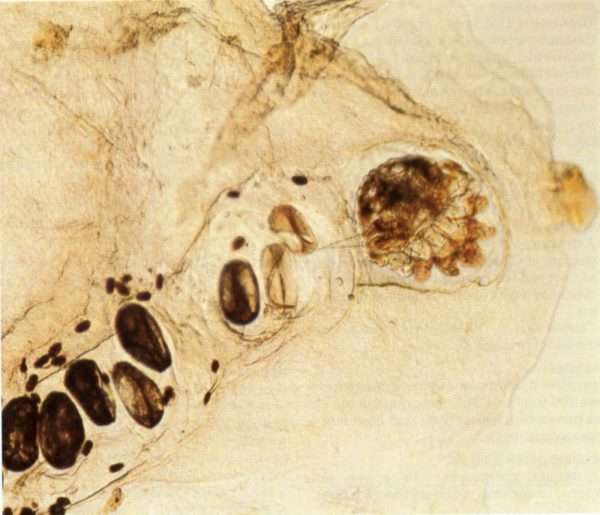

Возбудителем скабиеса является микроскопический эктопаразит, относящийся к отряду акариформных Он питается верхним слоем дермы. После попадания на дерму самка присосками прикрепляется к дерме и челюстями роет неглубокие вертикальные, S-образные ходы. В них паразит ежедневно откладывает по 2-3 яйца овальной форму, из которых через 3-4 дня появляются личинки.

Для роста личинкам необходимо питаться. После нескольких линек, через 17 дней нимфа становится половозрелой особью. Взрослые особи спариваются на поверхности. Самец после этого погибает, а самка остается фертильной в течение двух месяцев.

На протяжении женская особь роет ходы и откладывает яйца. Попадание на кожу только одной особи способно вызвать заболевание.

Паразиты травмируют дерму, откладывают экскременты, нарушая ее защитные функции. На участках с тонкой кожей особи проникают в мальпигиевый слой дермы, вызывая воспалительную реакцию. Резкое снижение местного иммунитета способствует быстрому распространению заболевания.

При попадании на кожу человека самки чесоточного зудня начинают оплодотворяться. После этого они проделывают в эпидермисе отверстие и, продвигаясь вглубь, выгрызают чесоточные ходы, где откладывают яйца. Как правило, одна самка за сутки откладывает по 2-3 яйца, из которых спустя 2 дня появляются личинки, а через пару недель вырастают уже взрослые особи.

Наибольшую активность клещи проявляют ночью. Именно в это время существует самая высокая вероятность подхватить заразу. Жизнеспособность и размножение паразитов возможно только на кожных покровах. За ее пределами клещи погибают через 2-3 дня.

Излюбленными зонами обитания и размножения у клещей являются запястья, ладони, стопы, мужские половые органы, а также внутренняя часть локтевого изгиба. Причина определенной локализации кроется в том, что эти места практически лишены волос. Слой эпидермиса на этих участках достаточно большой. К тому же здесь расположено множество потовых желез, которые выделяют пот. Таким образом, создается благоприятная среда для развития потомства.

В чесоточных ходах находятся не только яйца и личинки. Кроме потомства, самки чесоточных клещей оставляют здесь продукты своей жизнедеятельности. Являясь инородными для организма человека, такие вещества со временем провоцируют появление аллергических реакций, которые проявляются в виде кожного зуда. По причине того, что в ночное время паразиты наиболее активны, к вечеру зуд усиливается, а ночью становится просто нестерпимый.